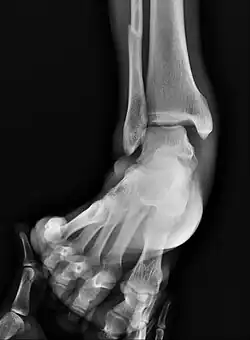

![]() | |

Fracture of both sides of the ankle with dislocation as seen on anteroposterior X-ray. (1) fibula, (2) tibia, (arrow) medial malleolus, (arrowhead) lateral malleolus | |